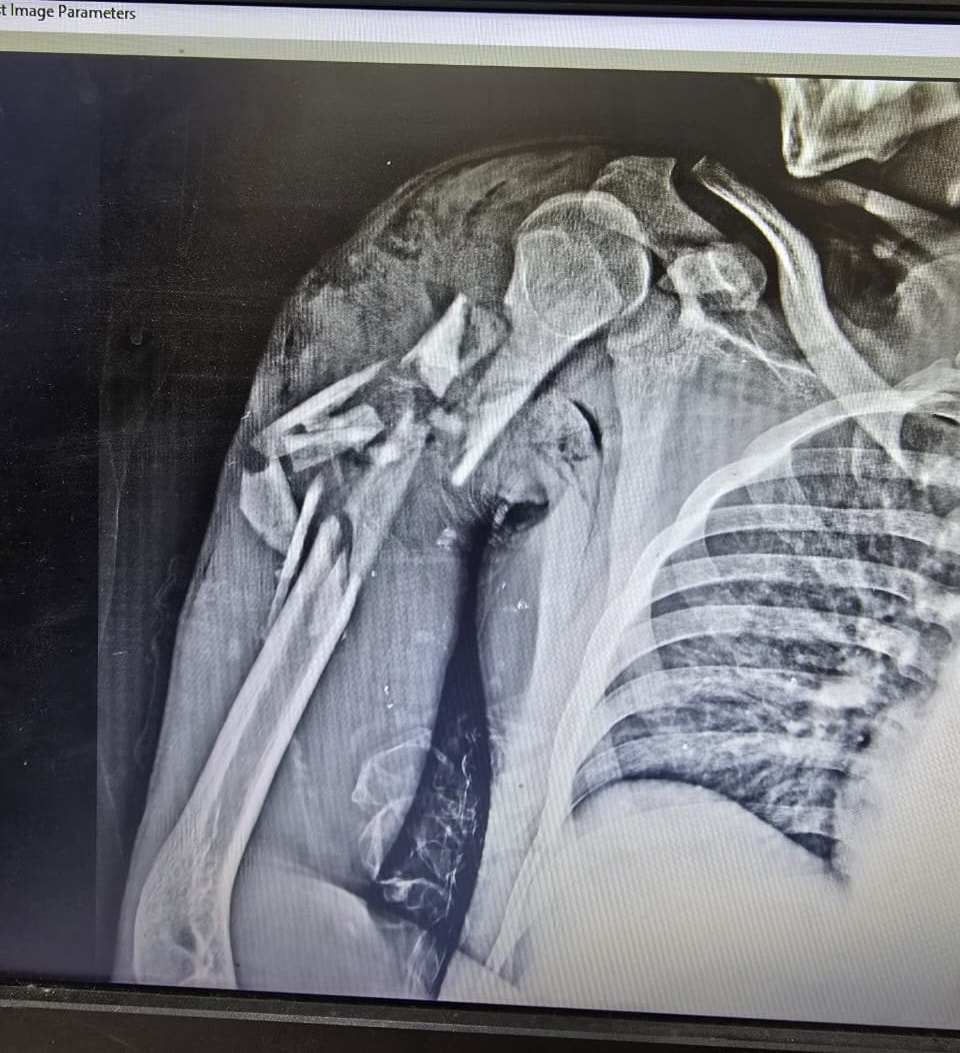

نجح فريق جراحي بمستشفى قها التخصصي، التابعة لأمانة المستشفيات المتخصصة بوزارة الصحة، بمحافظة القليوبية، في إنقاذ حياة شاب في الـ20 من عمره، اصطدم به قطار، وكاد الحادث أن يودي بحياته، وتسبب في إصابته بكسر متفتت مفتوح مع فقد جزء من العظام بالعضد الأيمن مع قطع بالعضلات، وكسر متفتت مفتوح مع فقد جزء من العظام بالساق الأيمن مع قطع بالعضلات، وتهتك بالقدم اليمنى وقطع بالأوتار والعضلات، مع كسر بعظام القدم.

وتابعت المستشفى، أنه تم تجهيز المريض ولياقته من قسم التخدير وتحضيره وتجهيز الدم والبلازما اللازمة للحالة، حيث استقر التشخيص علي كسر متفتت مفتوح مع فقد جزء من العظام بالعضد الأيمن مع قطع بالعضلات، وكسر متفتت مفتوح مع فقد جزء من العظام بالساق الأيمن مع قطع بالعضلات، وتهتك بالقدم اليمنى وقطع بالأوتار والعضلات، مع كسر بعظام القدم.

وأشارت، إلى أنه بدأت العملية قبل سطوع الشمس ليأتي يوم جديد ببارقة أمل وحياة تولد من جديد بفضل الله ورعايته، وتم عمل توصيل الأوتار والعضلات المتهتكة وتثبيت الكسور باستخدام مثبتات خارجية مع مسامير مجوفة وأسلاك معدنية، وسط تهديد واضح ببتر الساق لسوء حالة الجرح، ولكن جهود الفريق الطبي كان لهم رأي آخر واستطاعوا أن يعبروا بالشاب لبر الأمان.

كسور بجسم الشاب بعد الحادثكسور بجسم الشاب بعد الحادث

الأشعة الخاصة بالمريضالأشعة الخاصة بالمريض